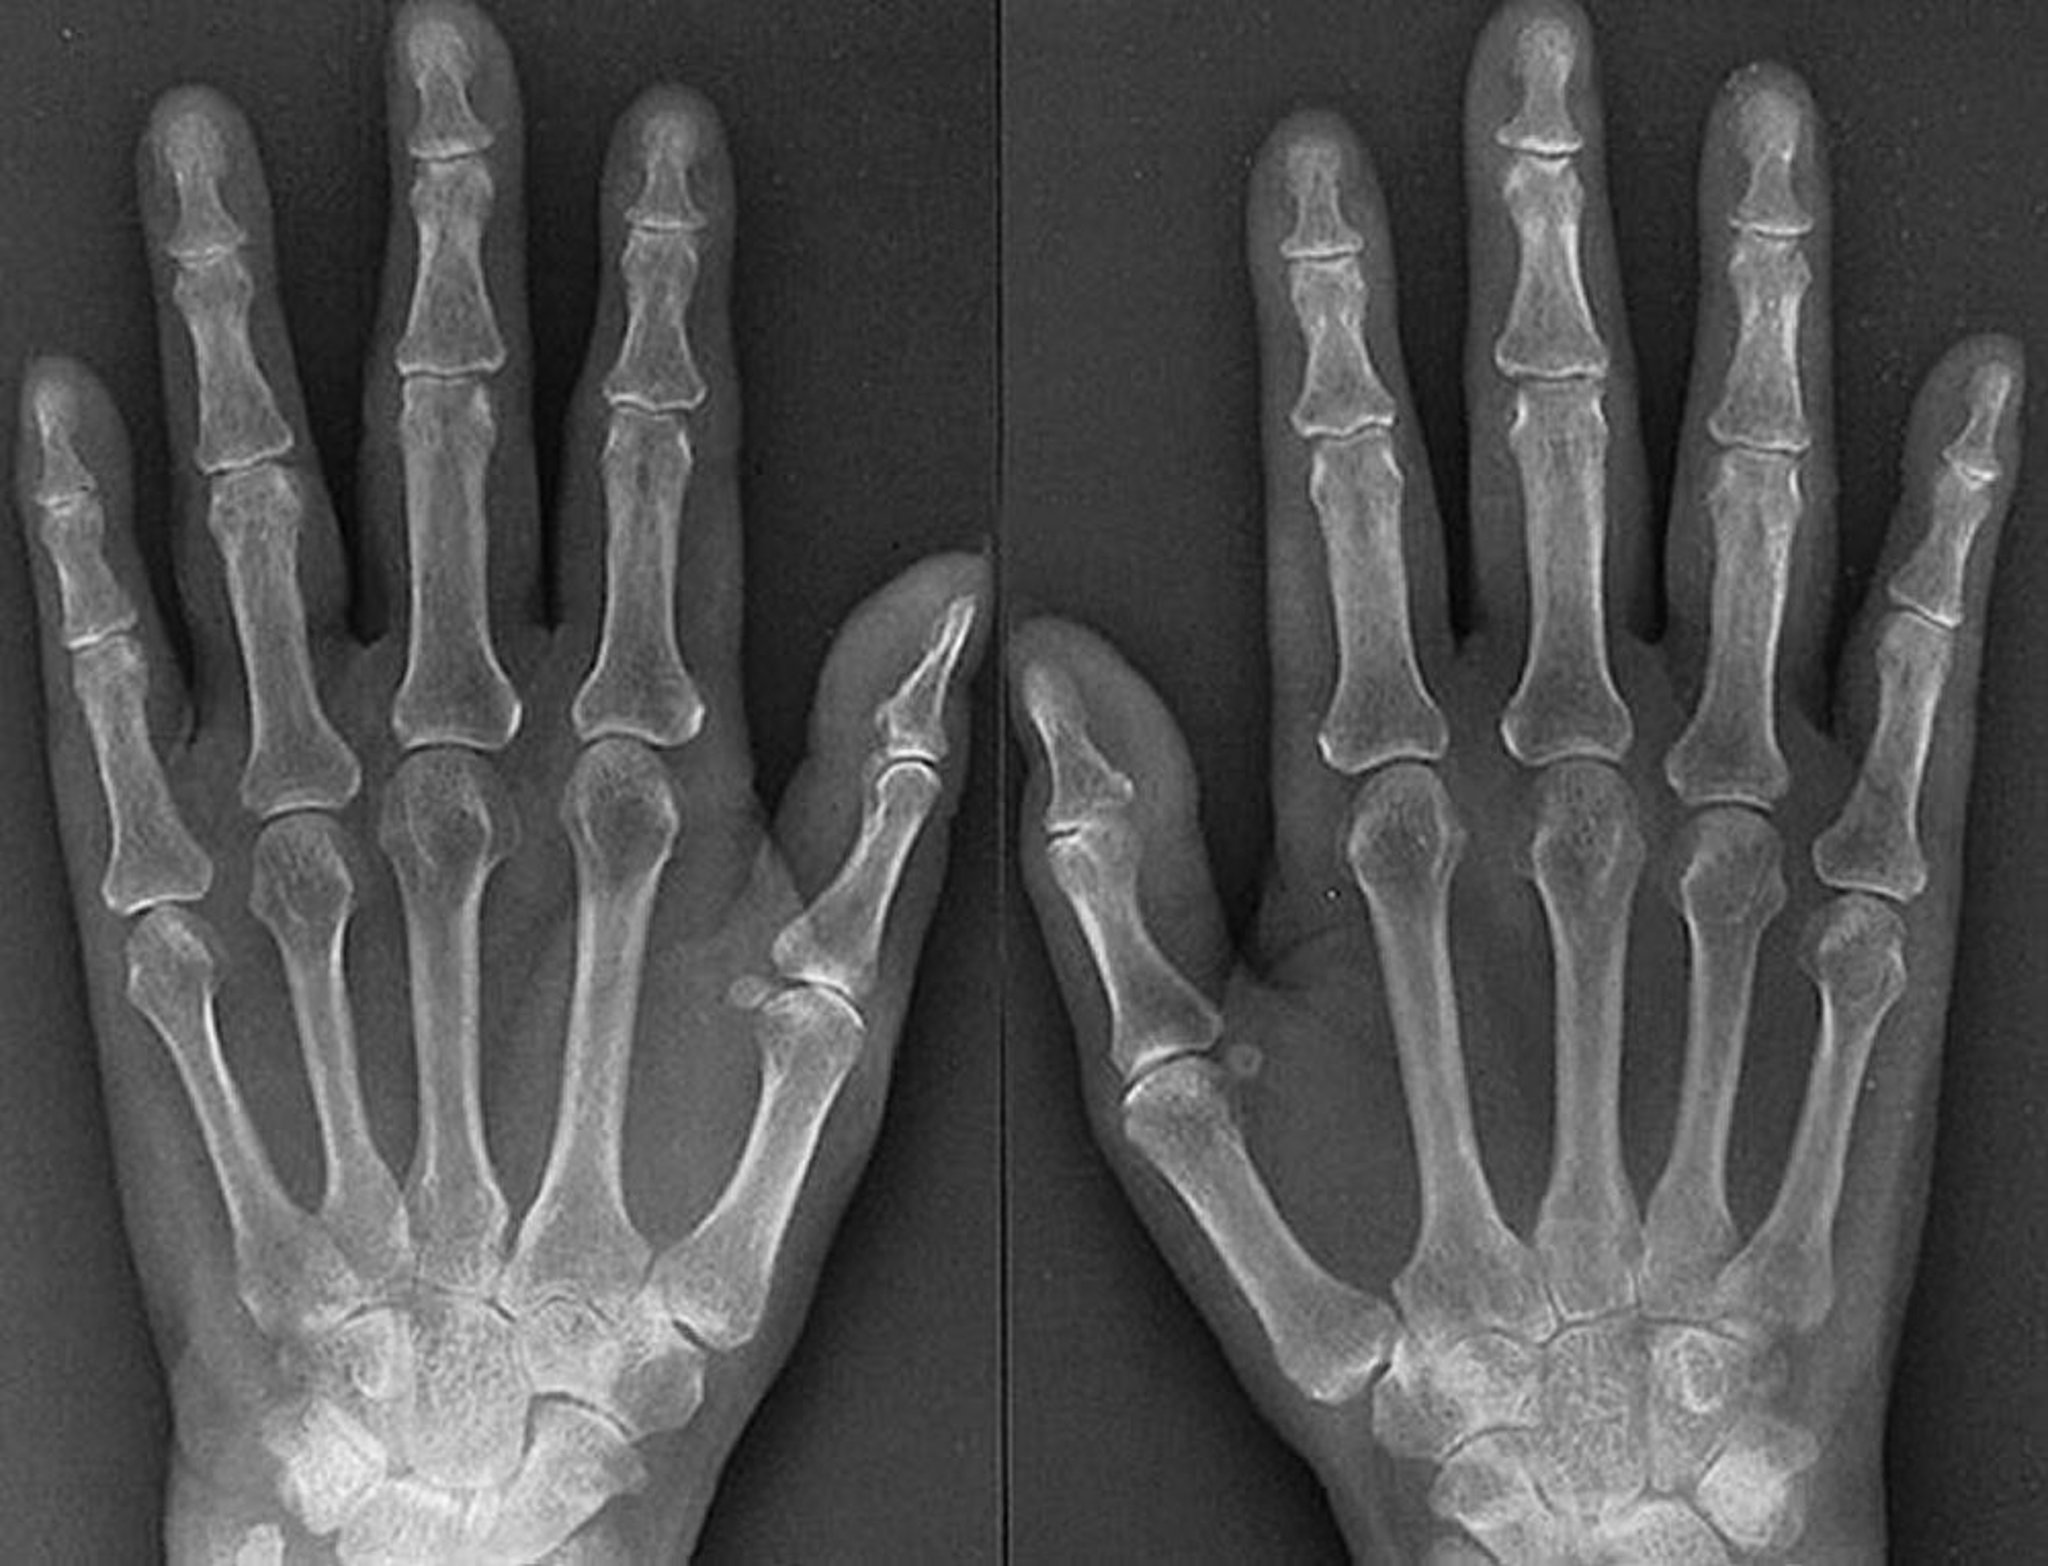

Características radiográficas da artrite reumatoide em fase inicial

As características da artrite reumatoide precoce agressiva, como vistas nessa radiografia de uma mulher de 61 anos de idade com RA por 1 ano, incluem evidências de edema de tecidos moles nas articulações metacarpofalângicas e interfalângicas proximais, osteoporose periarticular, estreitamento simétrico do espaço articular de várias articulações metacarpofalângicas e interfalângicas proximais de ambas as mãos e discretas erosões da 3ª articulação direita e da 4ª articulação metacarpofalângica esquerda e direita.